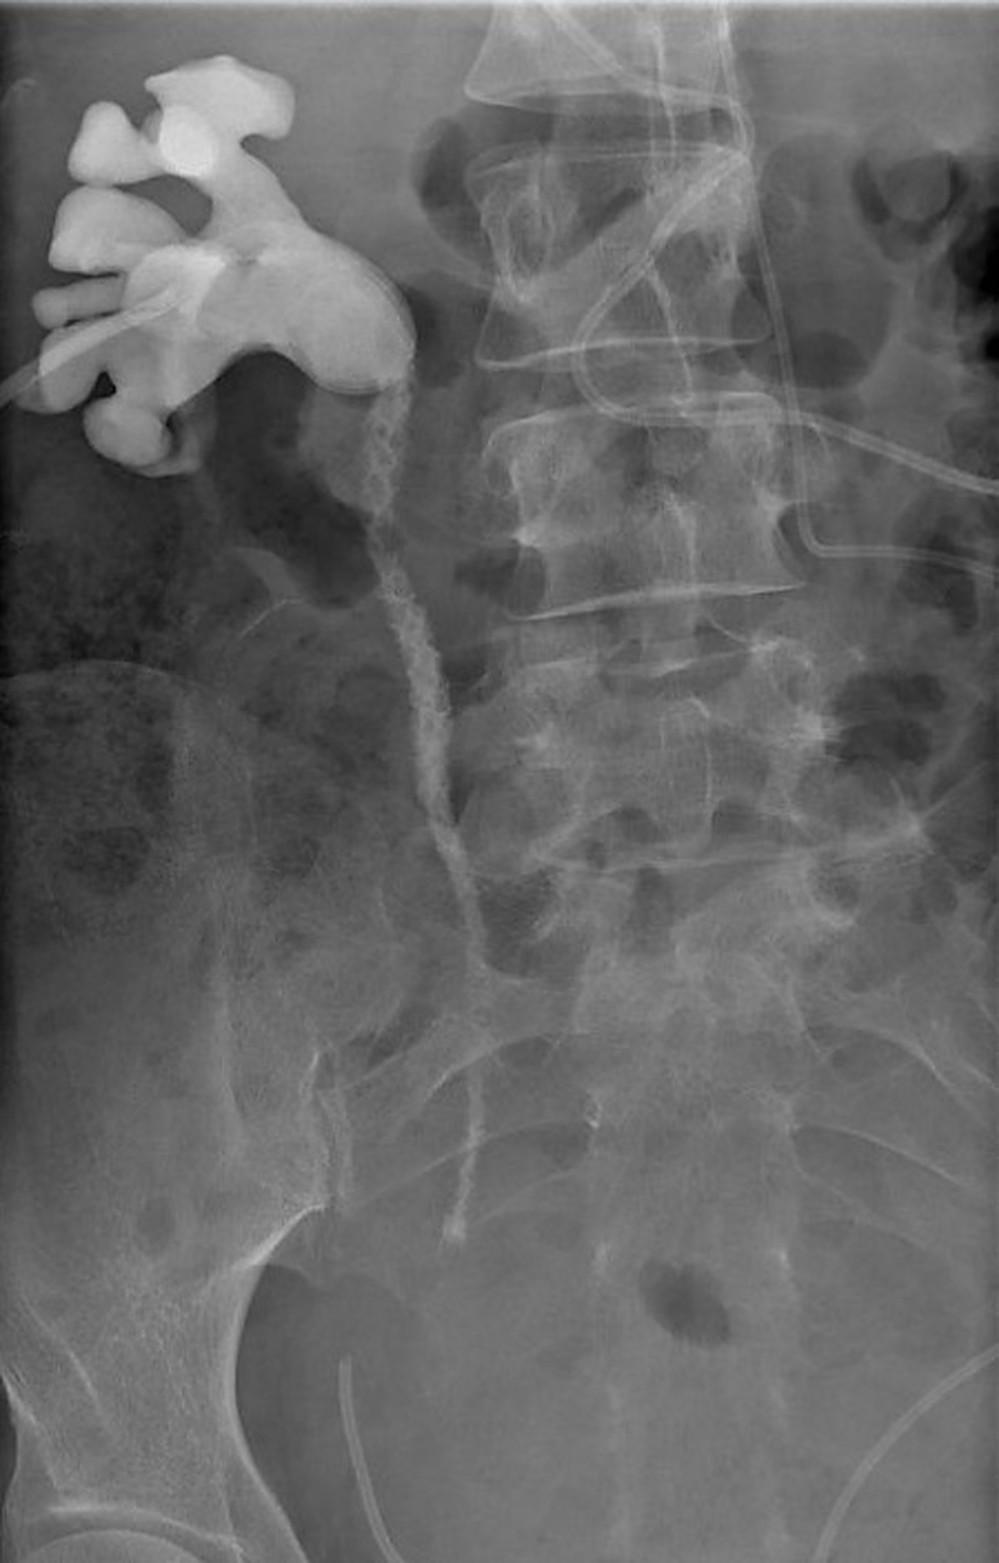

Een 38-jarige vrouw met urosepsis krijgt antibiotica en een nefrostomiekatheter vanwege afvloedbelemmering naar de blaas. Na verwijdering van de katheter vertoont het antegrade pyelogram een bijzonder beeld.